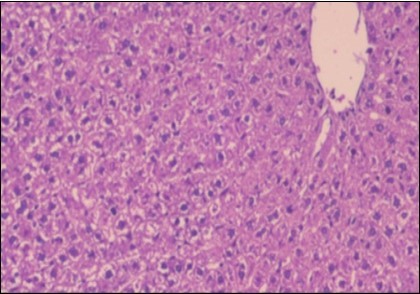

Effect of Ator, Fennel and Their Combination on the Liver of Obese Rats

The histological examination of the livers of control rats feeding standard diet showed normal architecture hepatocytes, blood sinusoid and central vein, figure 6. The rats which were fed on a (HFD), showed swollen hepatocytes with vacuolated cytoplasm filled with fatty infiltration, congested central vein and disappearance of blood sinusoids, figure 7. By comparison, the liver of rats that were treated by fennel after obesity and control mice observed nearly normal of the hepatocytes with eosinophilic cytoplasm, central vein and clear blood sinusoids and more bi-nucleated cells, figure 8. While examination of rats' liver that were treated by Ator and after the obesity appears, they showed mild fatty change in hepatocytes, few hepatocytes retain is eosinophilic cytoplasm and central vein figure 9. Liver of rats that were treated by fennel and Ator after obesity and control rats are showing nearly normal hepatocytes figure 10.

Figure 6.Photomicrogragh of liver section of control rat showing normal architecture Hepatocytes, blood sinusoid and central vein, (H&E) (40X).

Photomicrogragh of liver section of control rat showing normal architecture Hepatocytes, blood sinusoid and central vein, (H&E) (40X).